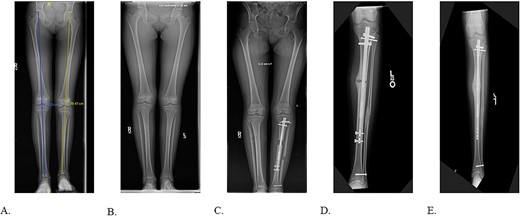

The patient had first presented to the orthopedic clinic at age ten due to limb length discrepancy (LLD) causing a progressively worsening limp. Initial hip to ankle scanogram identified that the left lower extremity (LLE) was shorter than the right by 3.1 cm (Fig. 1A). The patient underwent distal femoral and proximal tibial epiphysiodesis for the right lower limb with no complications. A year later the LLE was 2.5 cm shorter than the right (Fig. 1B). The patient then underwent left tibia and fibula osteotomy with insertion of a bone lengthening intramedullary rod which lengthened by 0.25 mm ×3 a day for eight weeks (Fig. 1C). A delayed union was identified nine months after the lengthening procedure indicating explantation of the two distal and one proximal interlocking screw for dynamization (Fig. 1D). Following the surgery, the patient recovered with osseous union, decreased pain, and improved gait (Fig. 1E).

A: 10.5-year-old female with fibular hemimelia, affected left side. B: 11-year-old female status post right distal femur and proximal tibia epiphysiodesis. C: 8-weeks status post left tibia/fibula osteotomy and PRECICE implantation. D: 9-month postoperative PRECICE implantation of left tibia with delayed union. E: 3-months postoperative dynamization of left tibia with osseous union.